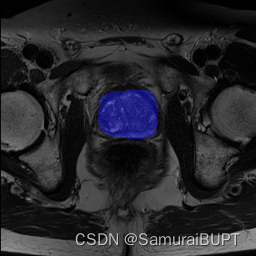

笔者目前正在做医学图像分割方向的开发,以下是我们用自己训练出的网络进行分割的结果:

使用Residual Unet网络训练的模型进行图像分割

使用ResidualUnet网络训练的模型进行图像分割

然后可以进行任意的图像分割演示。在前期的演示中,随鼠标移动,会产生不同的mask。鼠标左键是add mask,右键是remove area。在最初没有add mask时,处理结果与我们的训练成果已经相差无几。

笔者仅仅只是提供一个特例,实际上目前Segment Anything在我们数据集的其他图像上的表现,与实际ground truth仍然有较大差异,但是这样的开发思路的优秀以及其给Computer Vision界带来的变革,不可估量。